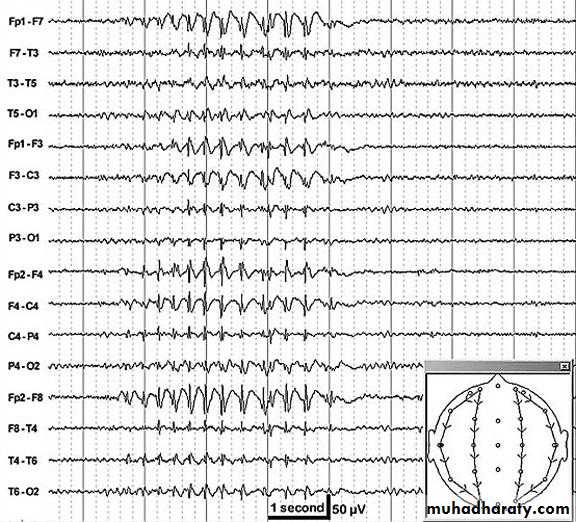

Interictal electroencephalogram

Hypsarrhythmia (seen in the image below) is the characteristic interictal EEG pattern. It consists of chaotic, high- to extremely high–voltage, polymorphic delta and theta rhythms with superimposed multifocal spikes and wave discharges.Medications such as ACTH, vigabatrin (may cause visual field defect) , and conventional antiepileptic drugs (AEDs) are the mainstay of therapy for infants with West syndrome. Unfortunately, no single medical treatment gives satisfactory relief for all infants with West syndrome.